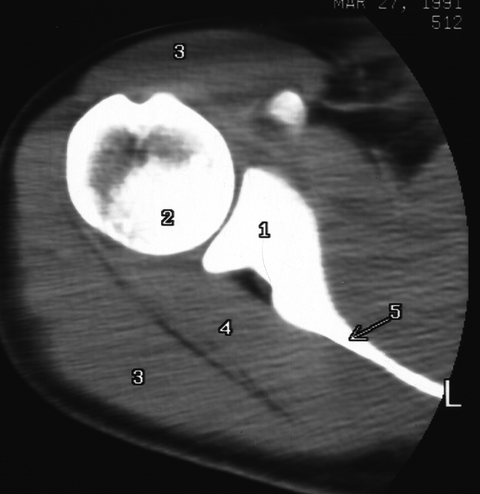

Shoulder CT 2

1. Glenoid

2. Humerus

3. Deltoid m.

4. Infraspinatus m.

5. Scapula